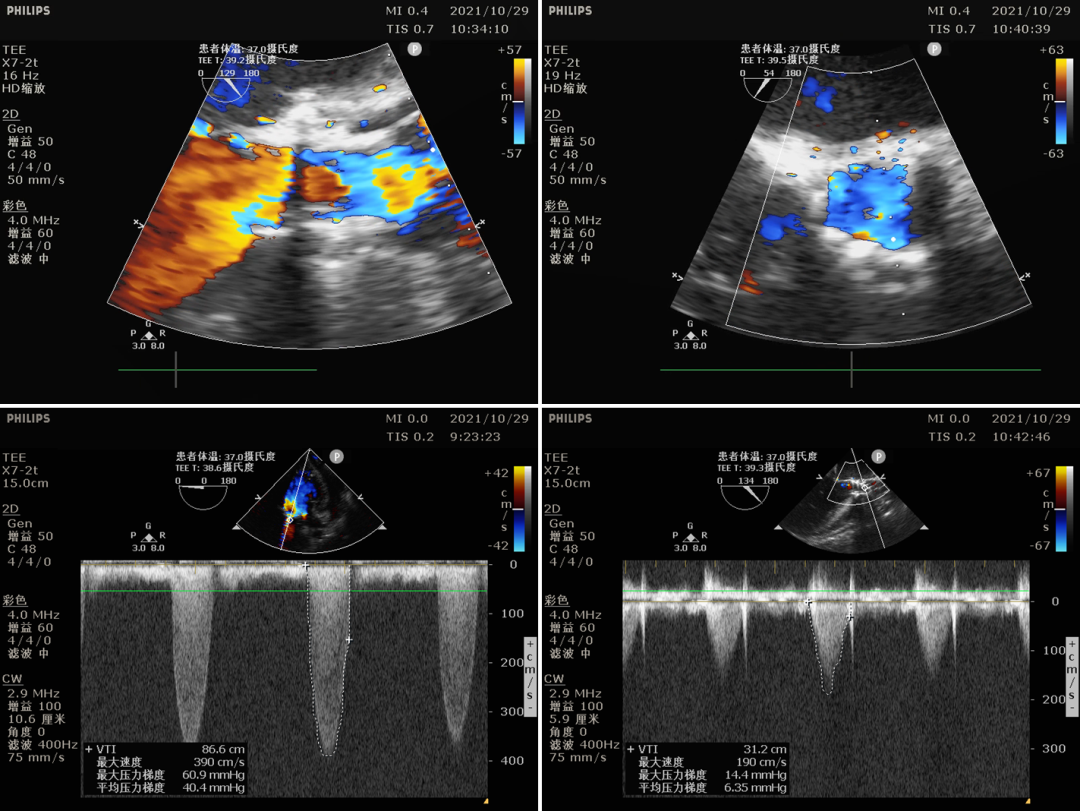

男性,72岁,主因“间断胸闷胸痛9年余,再发加重1月”入院,高血压病史;入院超声:重度主动脉瓣狭窄并中度关闭不全,Vmax 4.41m/s,PGmax 78mmHg,Pgmean 42mmHg,LADD 42mm,LVEDD 64mm,LVESD 44mm,LVEF 57%;NT-proBNP 2044pg/ml。

术后血流动力学

瓣膜工作状态良好,极微量瓣周漏,血流动力学有效改善